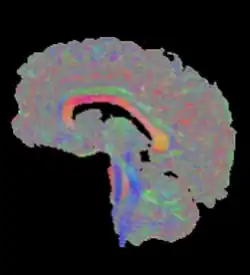

Außerdem wird die Richtung des größten Diffusionskoeffizienten häufig als Farbwert kodiert. Hierbei wird jeder der drei Achsen eine der Grundfarben rot, grün und blau zugeordnet, die bei dazwischen liegenden Richtungen gemischt werden.[4] Voxel ohne klare Hauptrichtung erscheinen grau (siehe Abbildung).

Als Traktografie oder Fiber Tracking werden Verfahren bezeichnet, die den Verlauf größerer Nervenfaserbündel rekonstruieren. Zur Visualisierung sind hierbei Darstellungen von Hyperstromlinien üblich, dreidimensionalen Linien, deren Verlauf der Richtung des größten Diffusionskoeffizienten folgt.[5][6] Die Abbildung am Beginn dieses Artikels zeigt beispielhaft alle Bündel, die die Medianebene schneiden. Einen alternativen Ansatz stellt die probabilistische Traktografie dar. Sie berechnet für jeden Punkt im Gehirn eine Wahrscheinlichkeit, mit der auf Grundlage der Daten eine Nervenverbindung mit einem gegebenen Ausgangsareal angenommen werden kann.[7] Derartige Ergebnisse eignen sich weniger für die Erzeugung aussagekräftiger Bilder, ermöglichen jedoch quantitative Aussagen und finden daher in der Kognitionsforschung Verwendung.